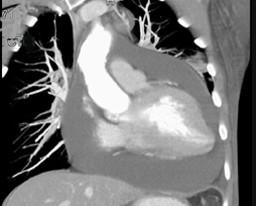

问题 男,28岁,胸闷气急,伴干咳,查体见颈静脉显露,CT如图,最可能的诊断为 ( )

选项 A、贫血性心脏病 B、心包转移瘤 C、心包积液 D、心肌炎 E、心包肥厚

答案 C